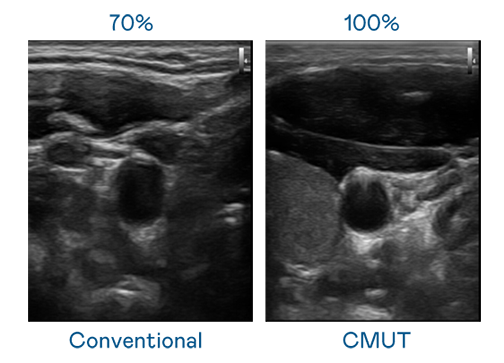

CMUT 技术是一种用电容式微机电元件来产生超音波讯号的技术。与传统 PZT 压电式技术相比,CMUT 频宽增加 30%,更宽频的超音波讯号让影像解析度大幅提升,是实现高影像品质医疗超音波扫描、促进精准医疗发展的关键技术。

超音波影像的解析度高低,首先取决于探头能发出的讯号频宽。1277星际电子 CMUT 可提供高清晰的超音波讯号,提供高频宽、高灵敏度、影像纹理细节更高的超音波影像,协助医护人员缩短影像判读时间及利用精准的医疗影像进行诊断。